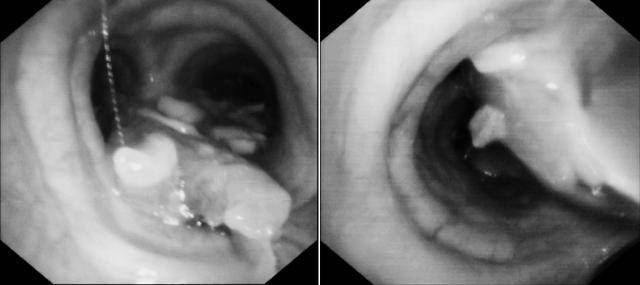

支气管镜探查所见,印证了情况的极端复杂性:大量食物残渣与黏稠分泌物致密嵌塞于主气管、隆突及双侧主支气管,常规吸引收效甚微。这不是一次简单的异物取出,而是对团队气道介入技术深度与精细化操作能力的极限考验。

(▲隆突、左右主支气管及分支管腔内被大量食物填充)

(▲气管套管外、咽腔喉腔内食物残渣)

在麻醉团队构筑的稳定生命支持平台上,呼吸与危重症医学科团队开始了如履薄冰的精细操作,利用电子支气管镜系统,实施了一套组合式介入方案:首先利用异物网篮套取大块、易活动的残渣;针对嵌顿紧密的异物,则以活检钳进行分次、精细钳取;同时辅以精准灌洗与吸引,清理深部分支的分泌物与碎屑。

(▲异物钳钳夹异物异物网篮取异物)